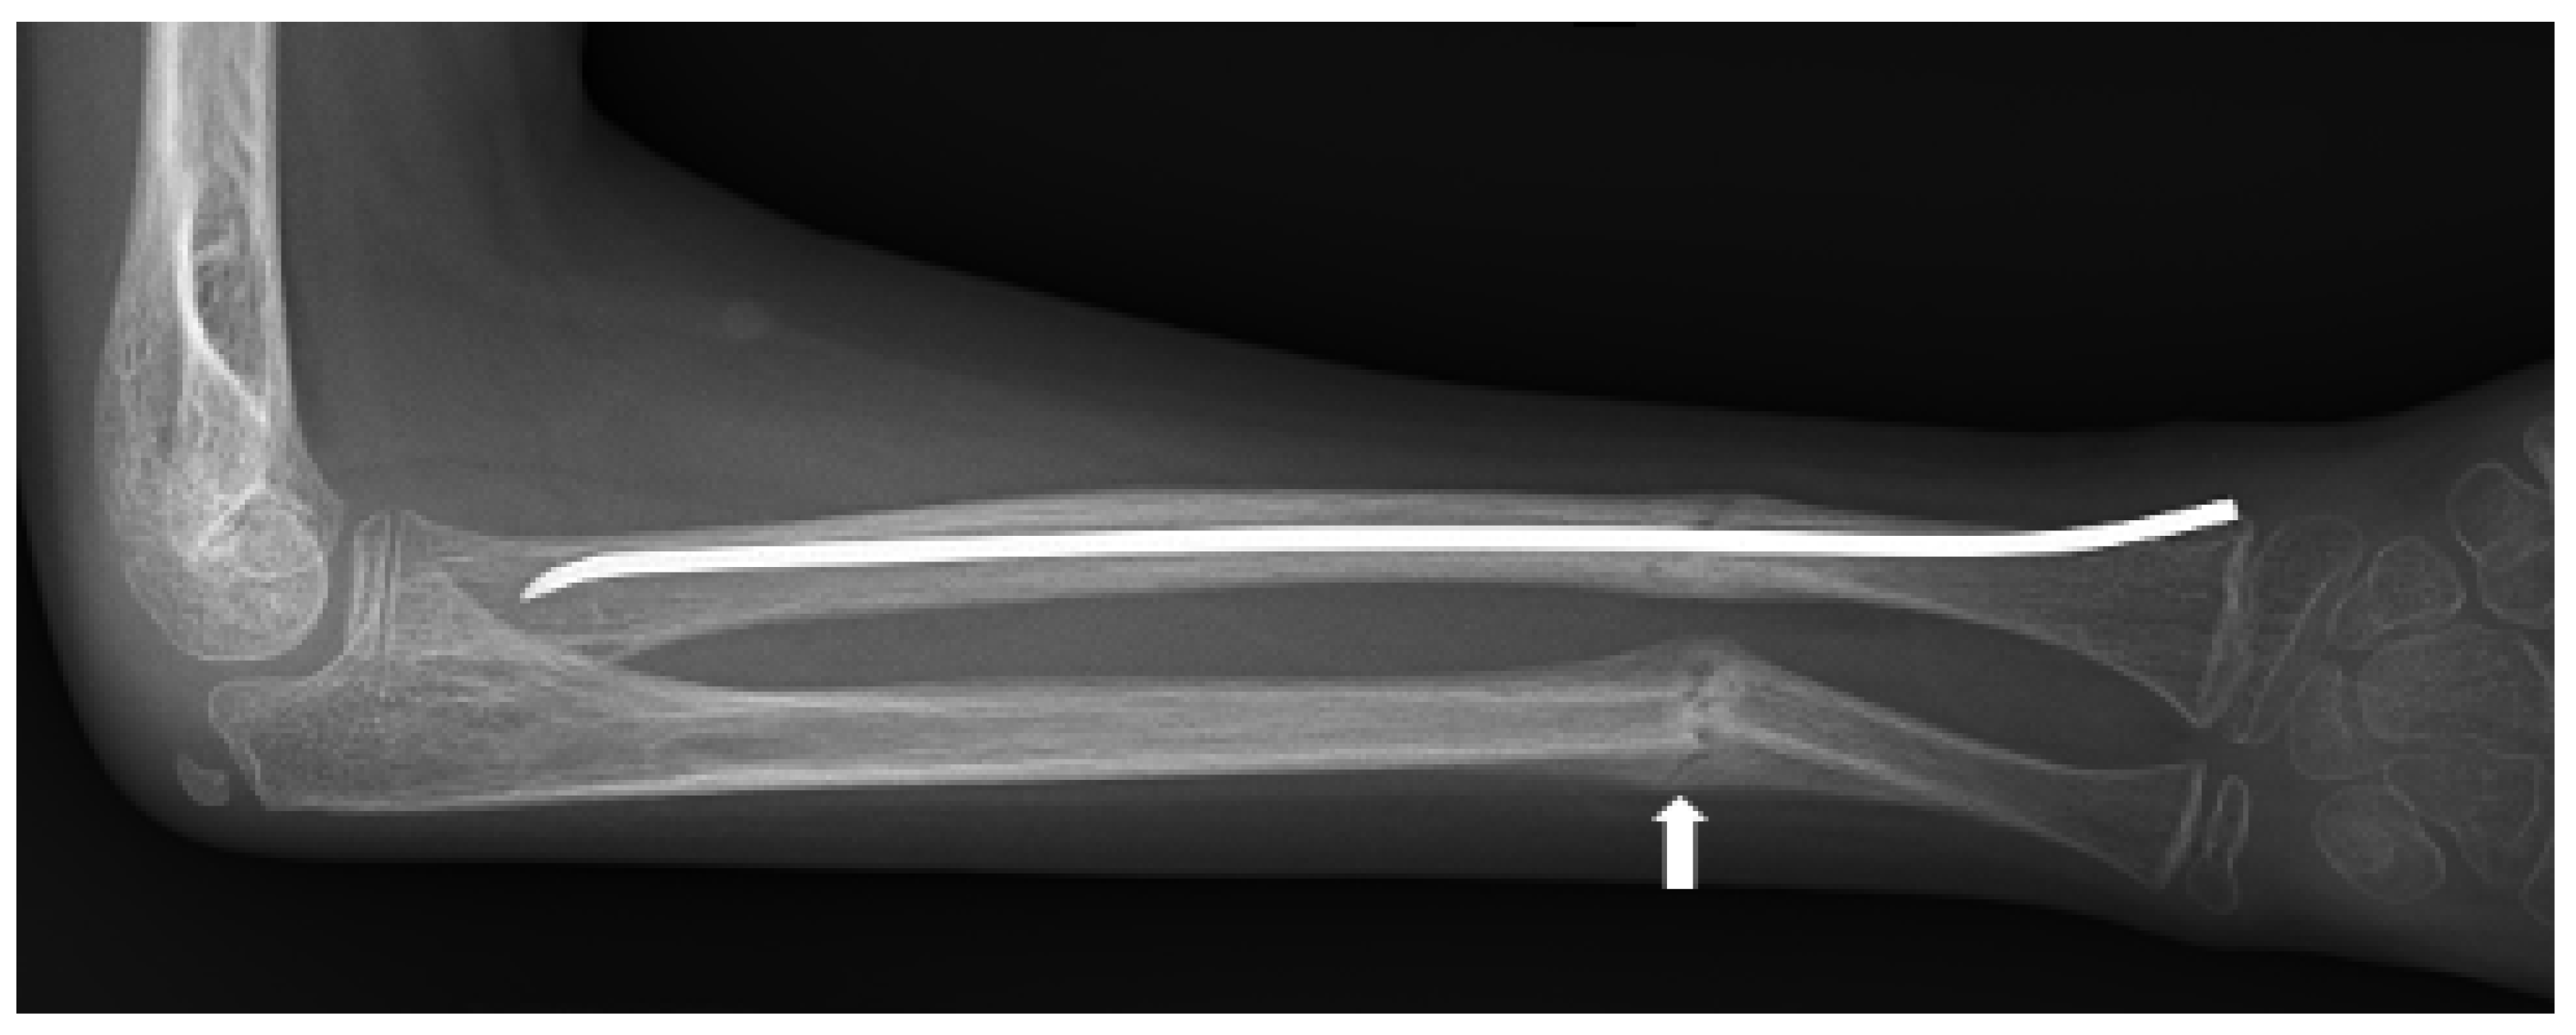

- Littman, J.; Phornphutkul, C.; Saade, C.; Katarincic, J.; Aaron, R. Osteoporosis, Fractures, and Blindness Due to a Missense Mutation in the LRP5 Receptor. Orthop. Res. Rev. 2023, 15, 39–45. [Google Scholar] [CrossRef] [PubMed]